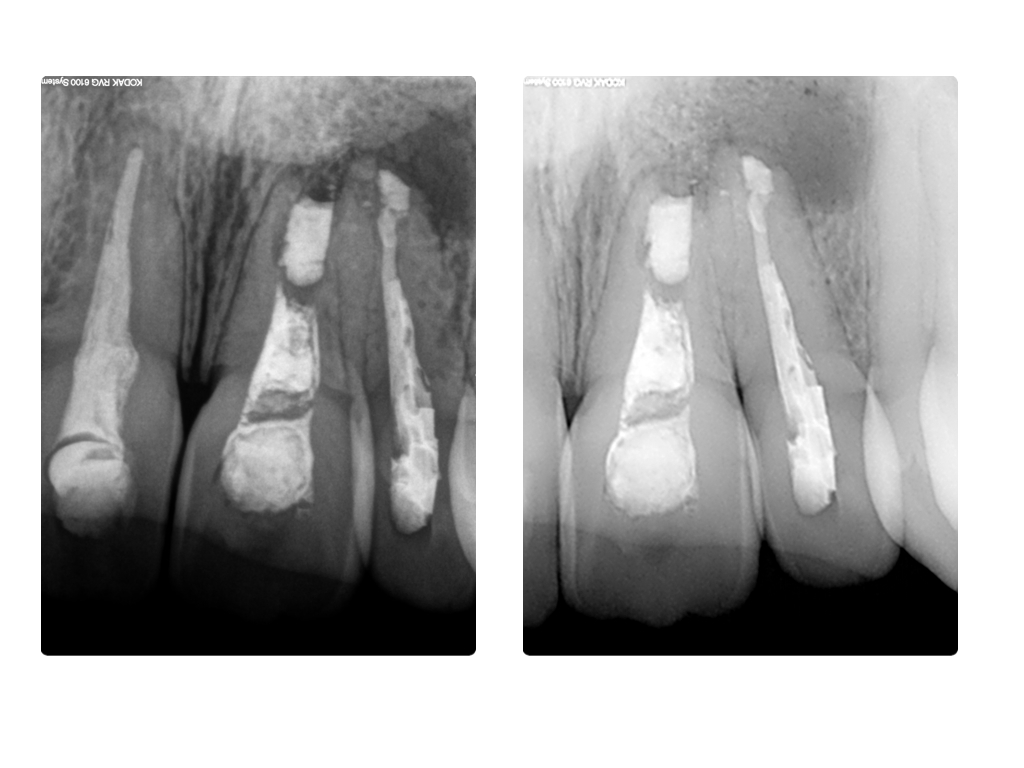

Einbahnstraße WSR